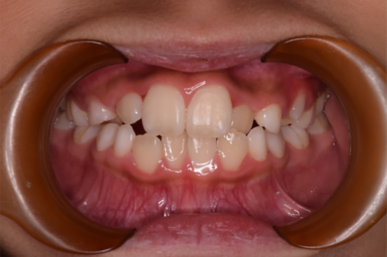

• Before

治療の開始が遅く、犬歯と奥歯の生え代わりが始まっていましたが、床矯正より治療スピードが早いアライナー矯正を使用して、犬歯のスペースをとても短期間に作ることができました。八重歯を防げましたので固定式の装置は必要なくなりました。永久歯がすべて生えるまでは予防歯科で歯の生え代わりと機能を管理します。